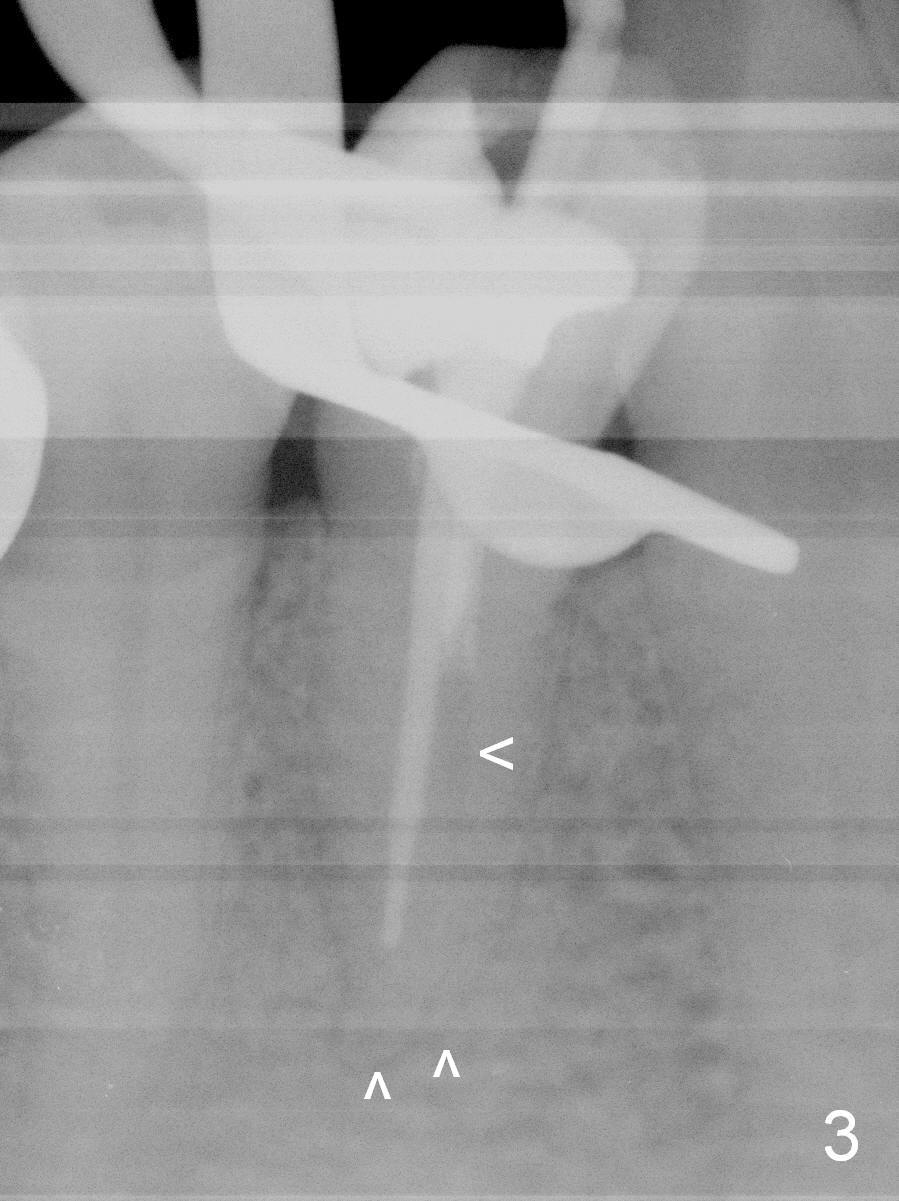

Further exploration finds a lingual canal (Fig.2), which is debrided until 30 hand file. When the canals are being filled with gutta percha and paste, the lingual canal is not filled (Fig.2). After removal of buccal gutta percha, the lingual canal is enlarged with 30/.04 rotary file and filled (Fig.4). The lingual canal is laterally condensed; composite build up is finished (Fig.5).

In fact CBCT has ben taken for #14 RCT and is reviewed prior to this case. If CT were reviewed, finding the extra canal would be easier (Fig.6 coronal section). It appears that the apical canals are blocked (Fig.7). The canal is split at the middle of the root, as shown in Fig.8,8' (axial upper section, as shown by the upper dashed line in Fig.6) and in Fig.9,9' (axial lower section, as shown by the lower dashed line in Fig.6). The buccal canal should not have been debrided with 40/.04 rotary file (30/.04 would have been better). In all, the tooth has two fused roots (Fig.3,9,9').